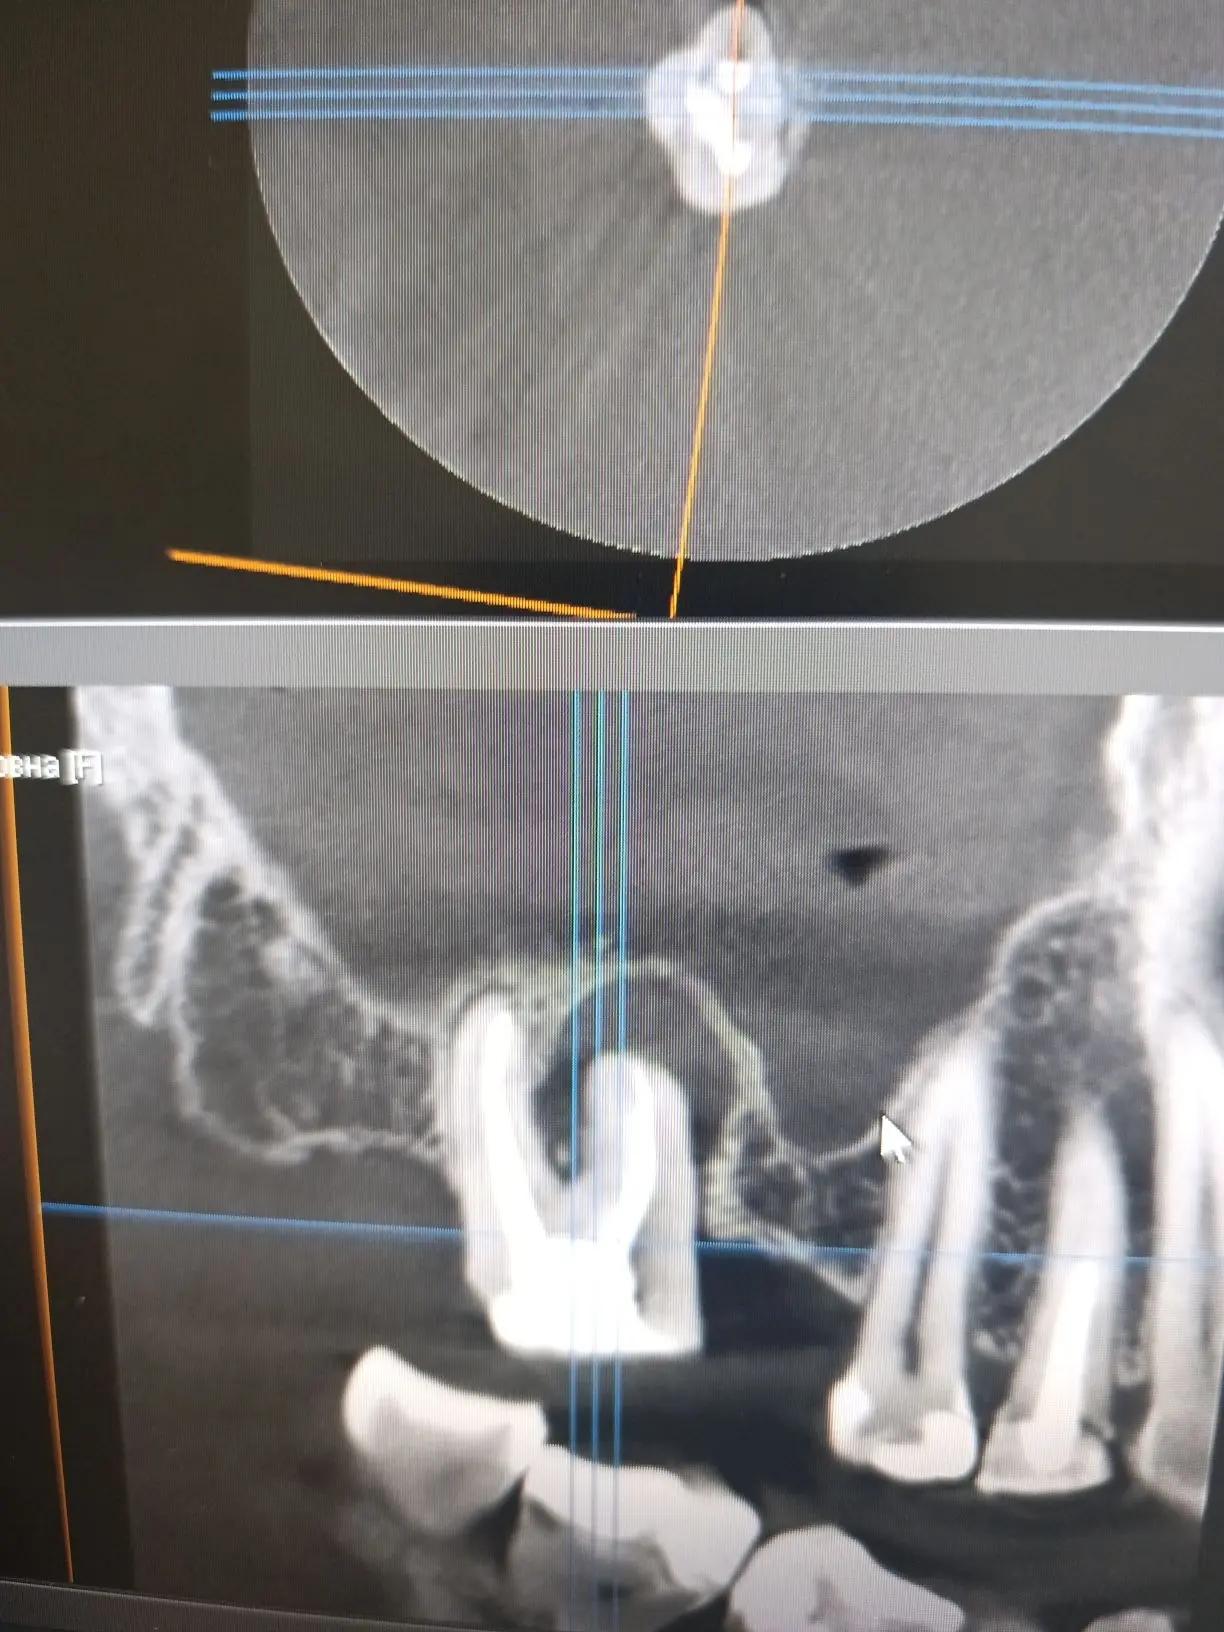

Добрый день! Возможно ли вылечить воспалённый зуб (снимок прикреплен) без удаления? Врач назначил антибиотики и обезболивающее с последующим удалением зуба. Можно ли сохранить и вылечить зуб с таким воспалением?